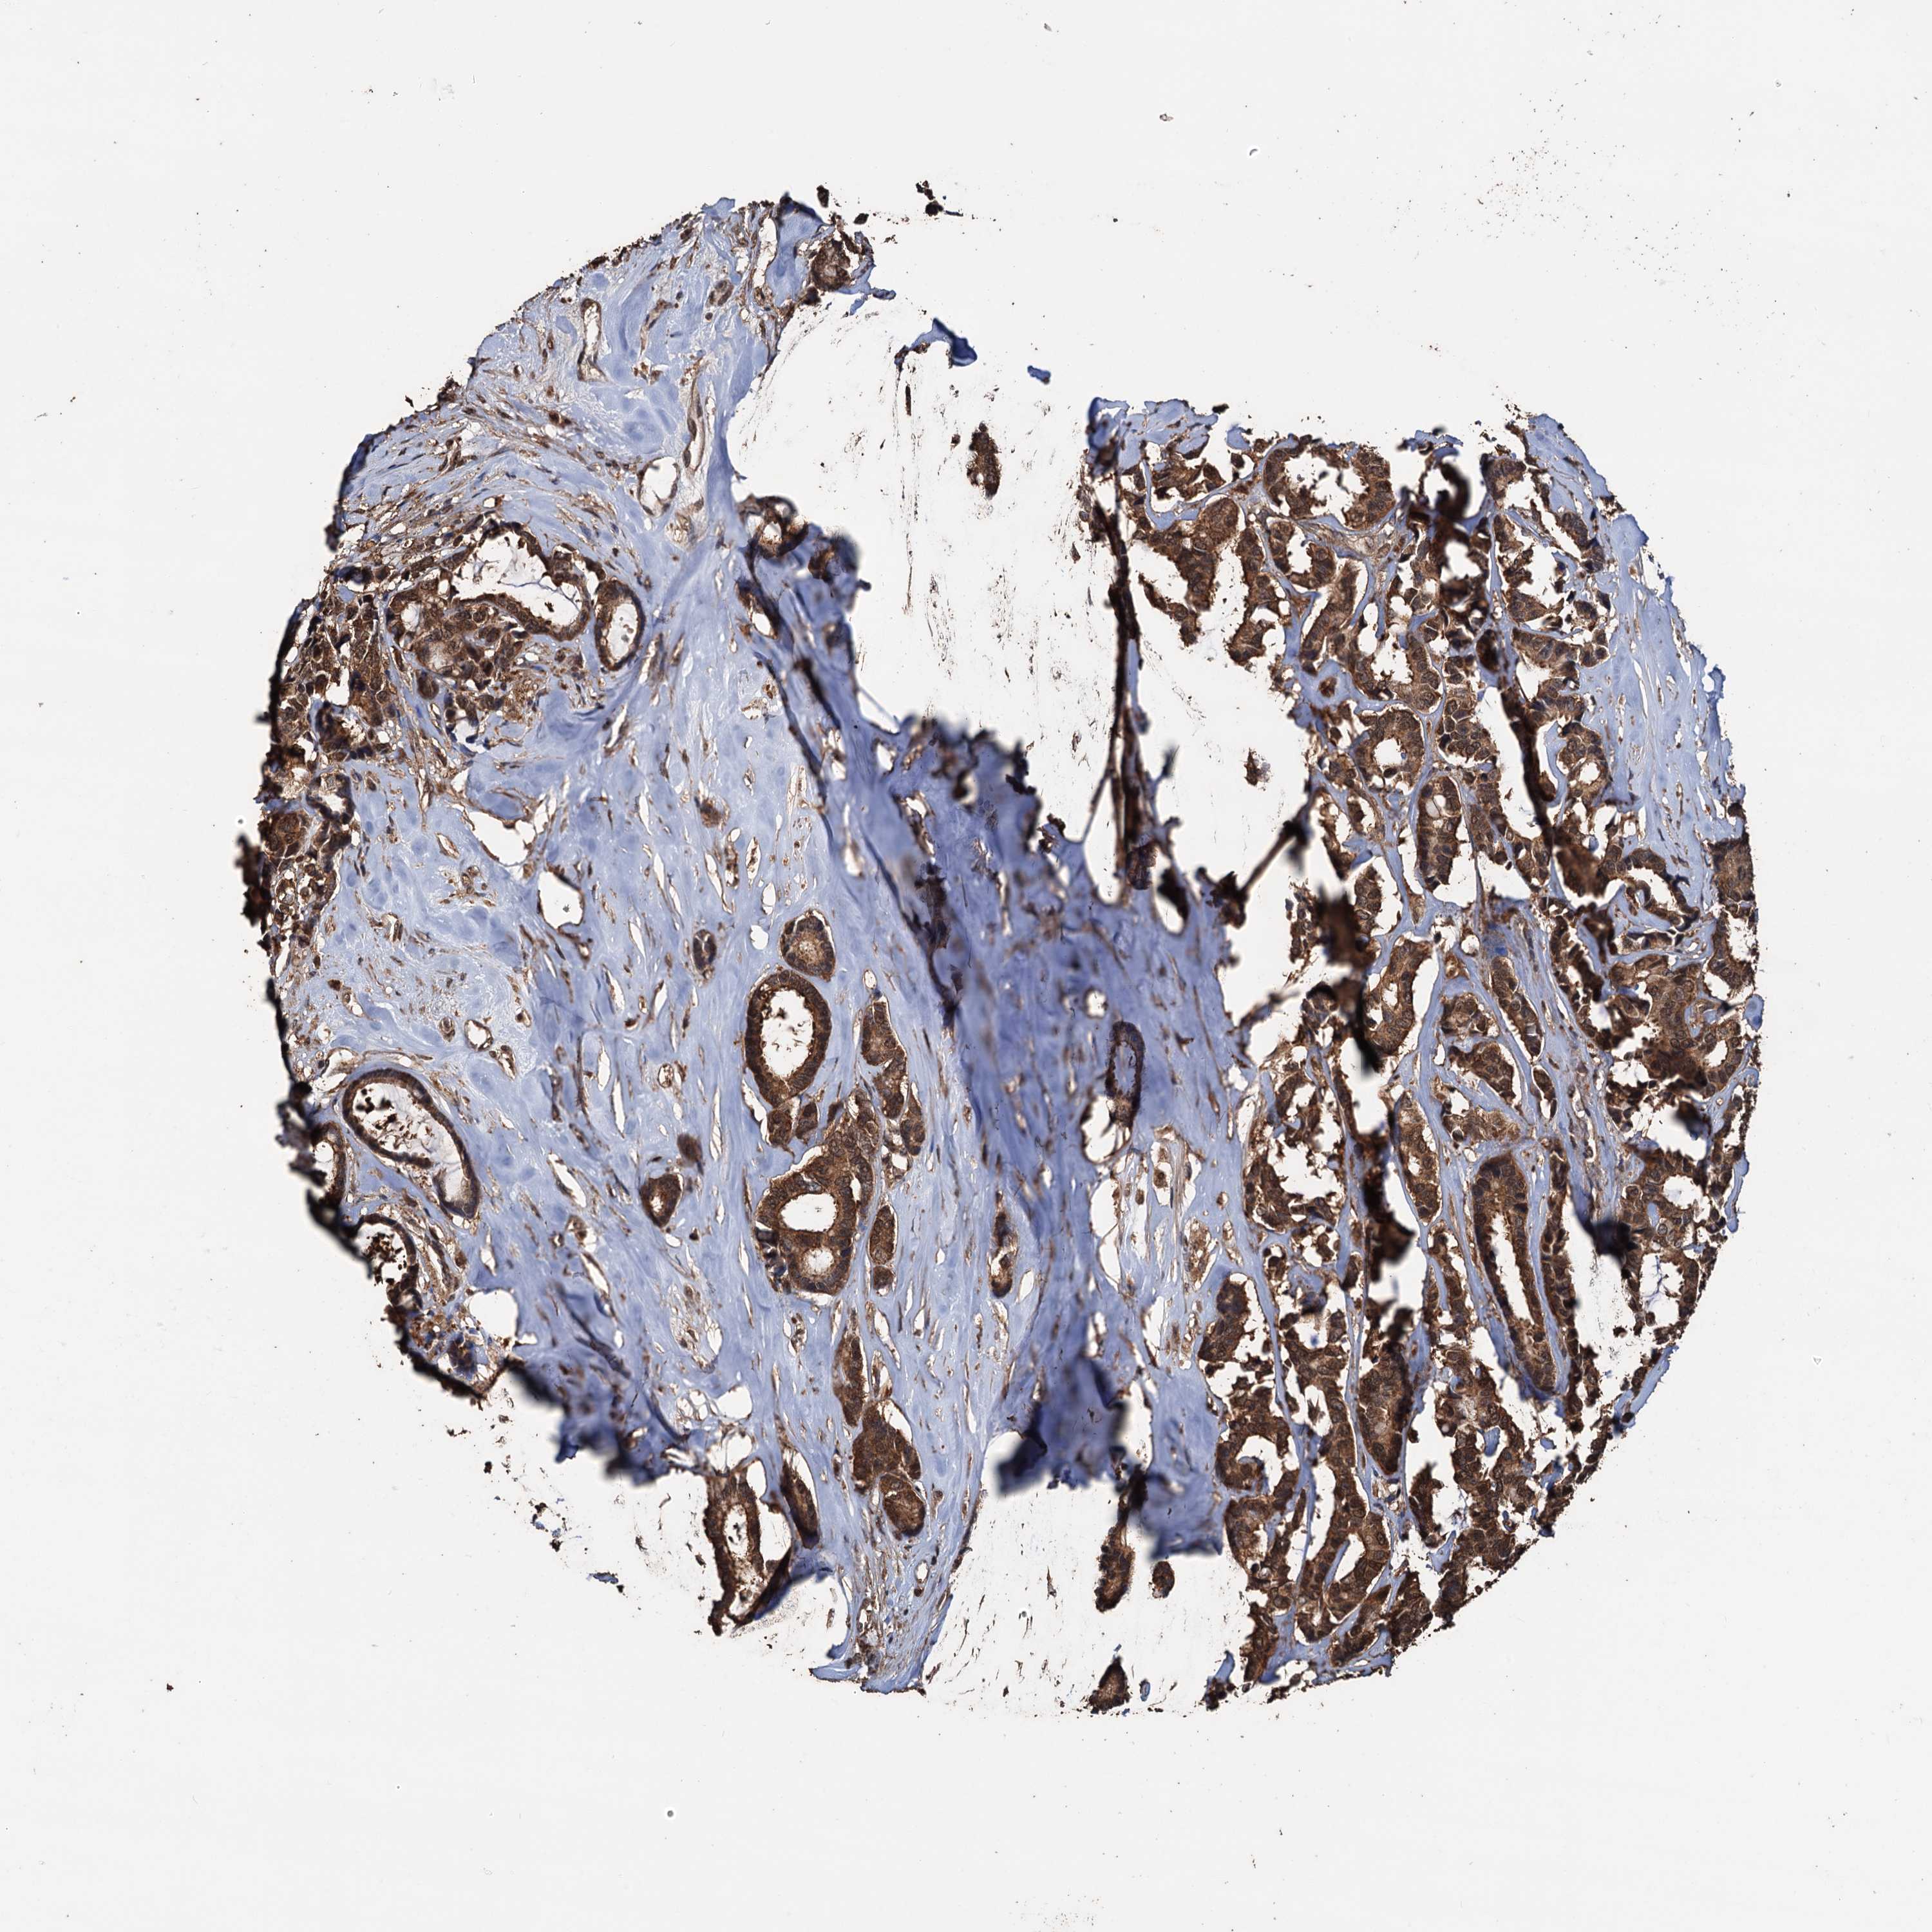

CANCER BREAST CANCER Show tissue menu

BRCA TCGA BRCA VALIDATION PROTEIN EXPRESSION

Breast cancer

Human cancer